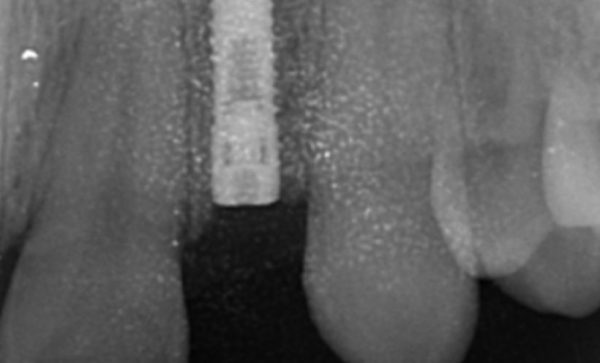

Sukal has been my dentist for many years, from simple check ups to a dental implant! I have always felt comfortable in the dentist chair and happily watched the TV on the ceiling while work is done on my teeth and never once felt any pain and always felt comfortable. I would never go anywhere else! Thank you all for being kind, caring and helpful at all times :-) Sarah Galloway